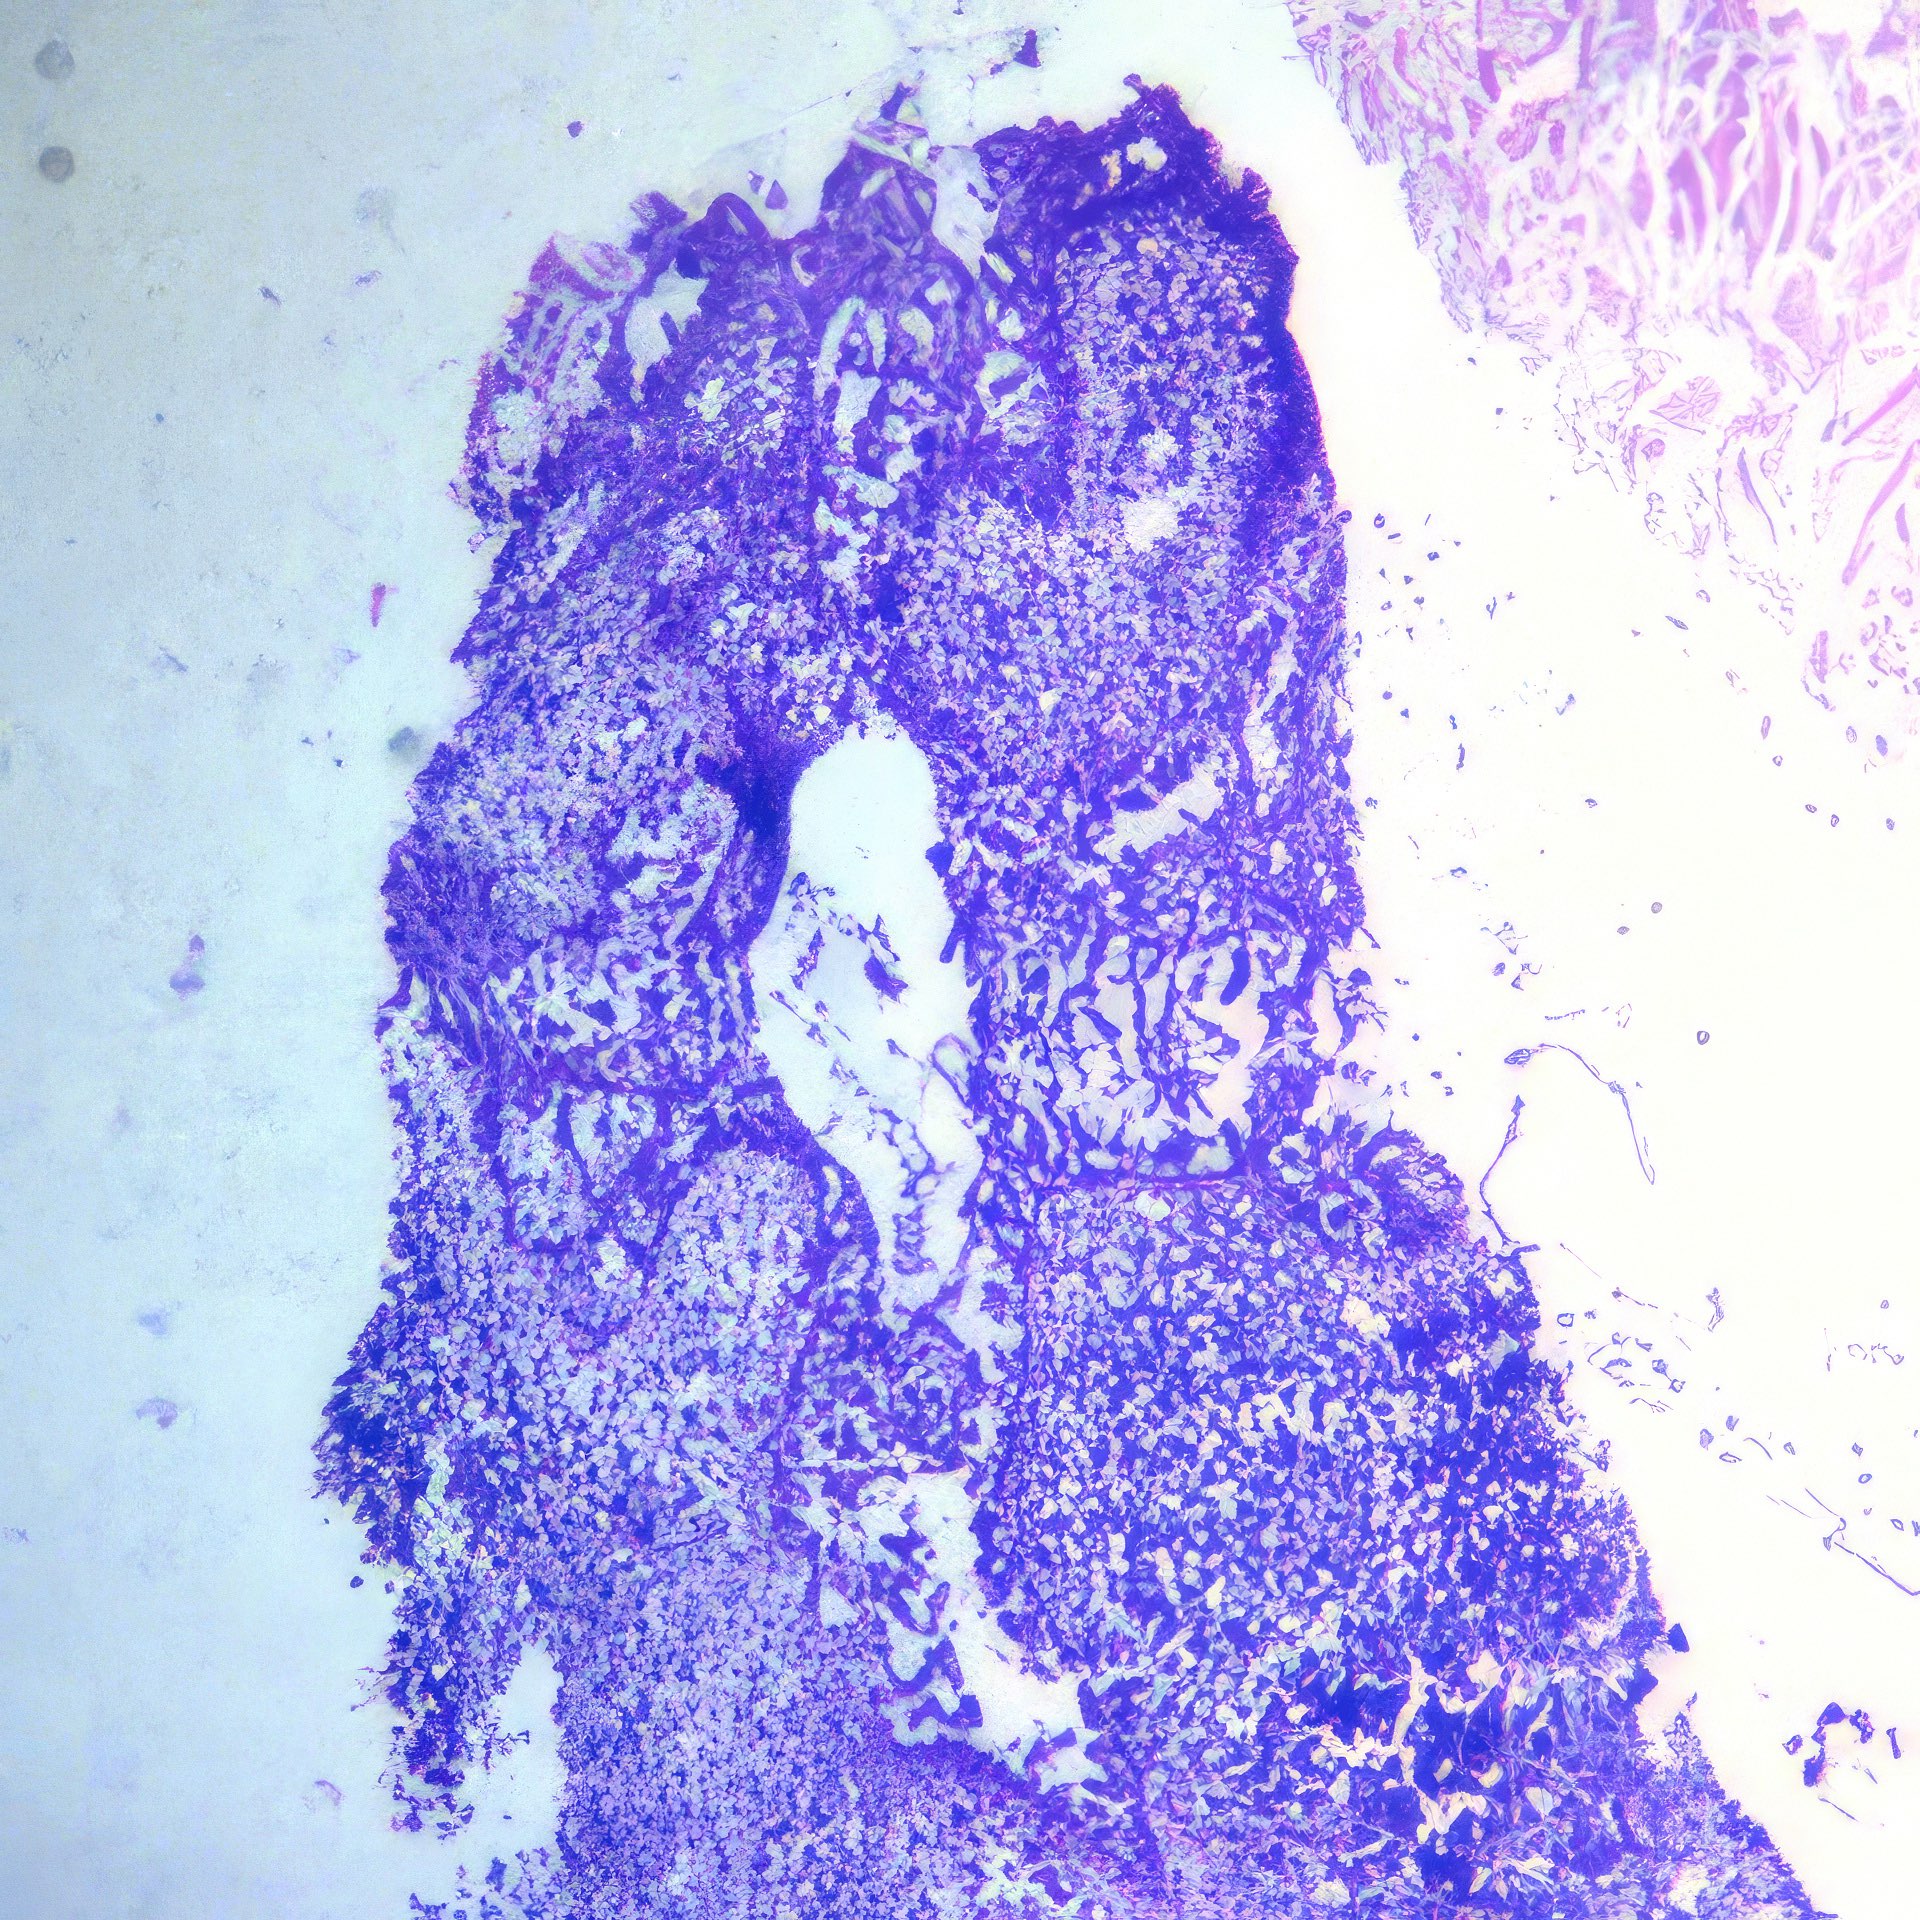

Abbildung 1 – 4: HE-Färbung; 1 – 4, original Obj. 40x, Abb. 4:

zusätzlich vergrößert

Histologie

Die histologischen Bilder (Abb. 1 und 2) bestätigen die zytologische Diagnose. Weite Teile des Gewebes sind durchsetzt von Tumorzellen, die nur angedeutet Verbände bilden und deutlich polymorphe Kerne aufweisen.

Abbildung 1 und 2: Histologische Bilder desselben Falles, HE-Färbung, Abb.1: Obj. 10x, Abb. 2: Obj. 20x